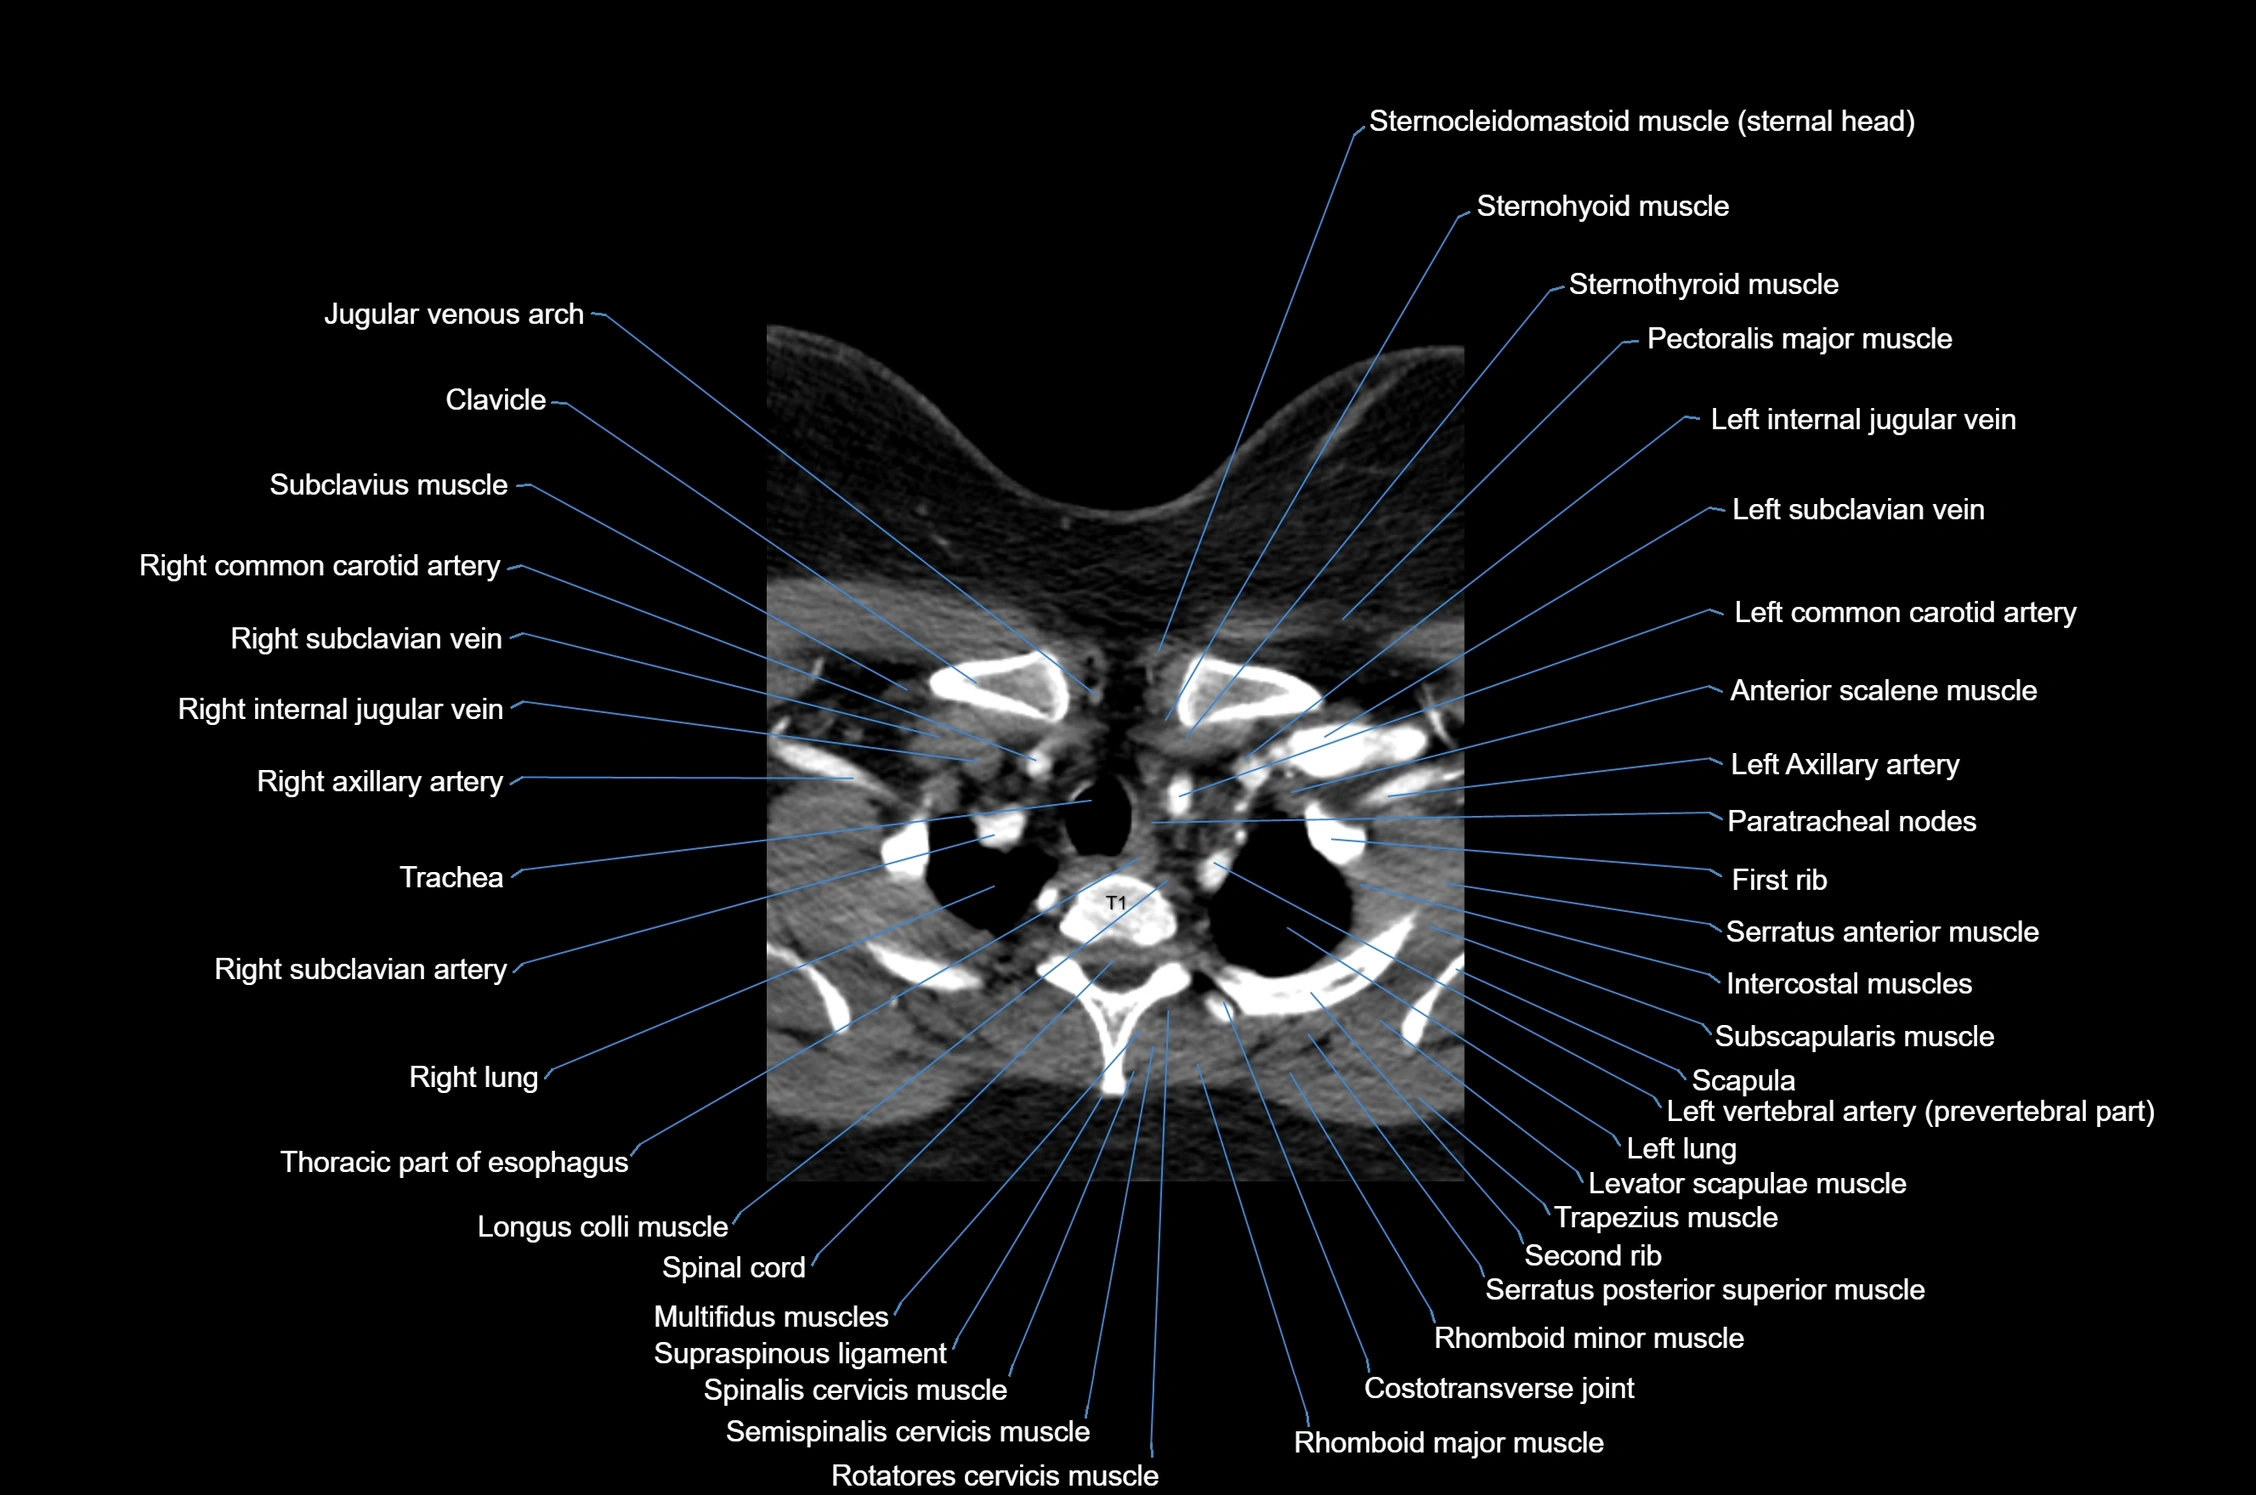

- Axillary artery

- Clavicle

- Costotransverse joint

- First rib

- Intercostal muscles

- Jugular venous arch

- Levator scapulae muscle

- Longus colli muscle

- Multifidus muscles

- Paratracheal lymph nodes

- Rhomboid major muscle

- Rhomboid minor muscle

- Right subclavian artery

- Right subclavian vein

- Rotatores cervicis muscle

- Semispinalis cervicis muscle

- Serratus anterior muscle

- Serratus posterior superior muscle

- Spinal cord

- Spinalis cervicis muscle

- Supraspinous ligament

- Thoracic part of esophagus

- Trachea

- Trapezius muscle